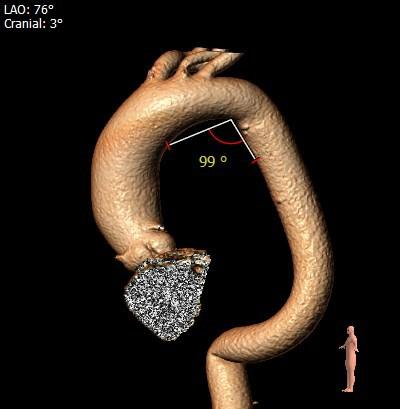

主动脉根部评估

根部概览

外周分析